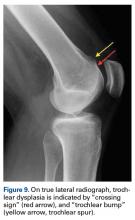

Figure 9.